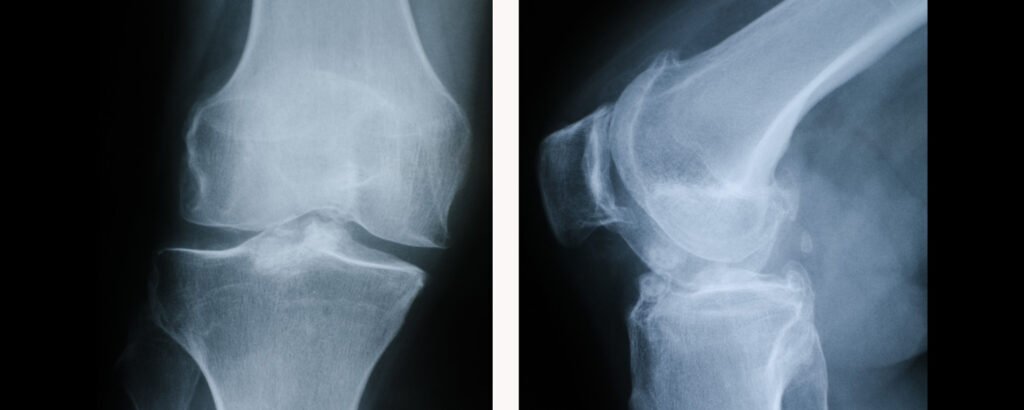

A artrose, também conhecida como osteoartrite ou osteoartrose, é uma doença degenerativa caracterizada pelo desgaste progressivo da cartilagem articular. A cartilagem é o tecido liso e resistente que reveste as extremidades dos ossos, permitindo que deslizem suavemente um sobre o outro durante o movimento. Quando esse tecido se deteriora, os ossos começam a atritar diretamente, causando dor, inflamação e limitação funcional.

No joelho, a artrose afeta principalmente três compartimentos: o femorotibial medial (parte interna), o femorotibial lateral (parte externa) e o patelofemoral (entre a patela e o fêmur). O processo degenerativo não se limita apenas à cartilagem – envolve toda a articulação, incluindo o osso subcondral, ligamentos, cápsula articular, membrana sinovial e músculos periarticulares.